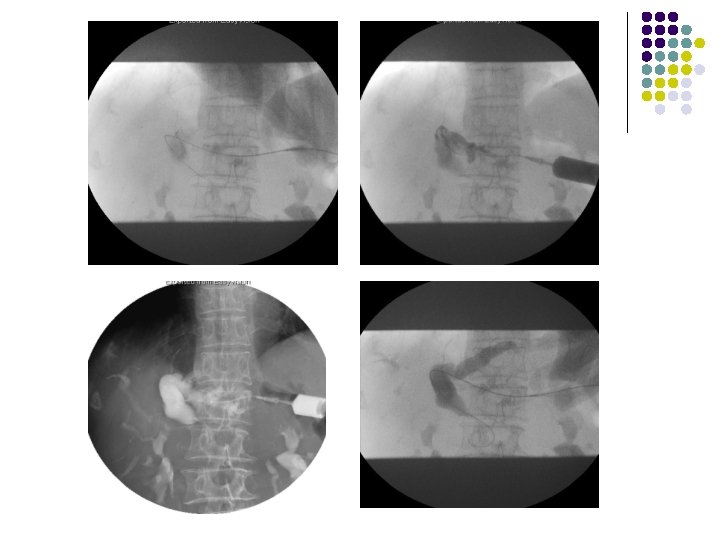

Procedure l 超音波定位 l plain film l 消毒 l 局部麻醉